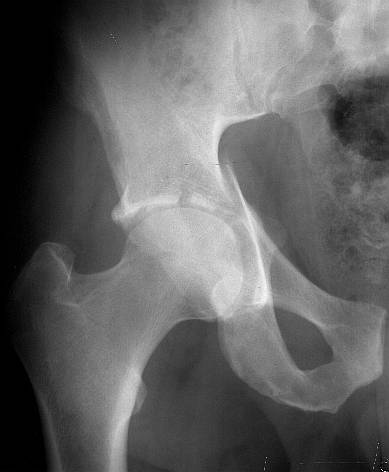

The iliac oblique reveals a displaced fracture of the posterior column, and it appears that the femoral head is not congruous with the acetabulum.

AP, obturator oblique films and a CT scan will better reveal the extent of the injury.

IMHO, it' s a transverse fr.